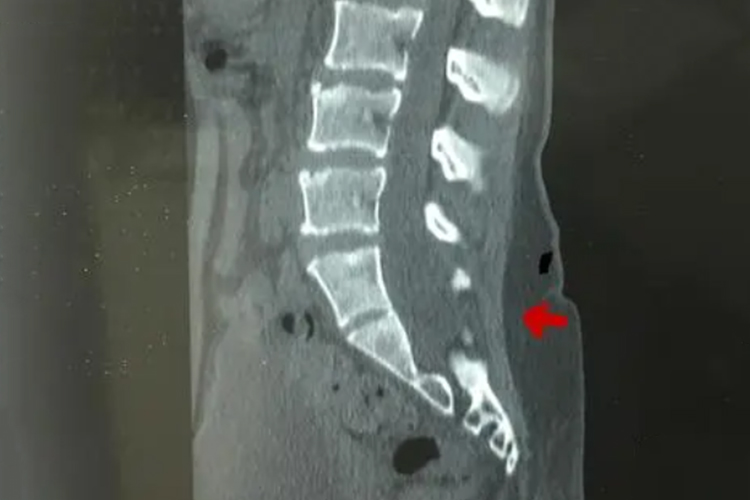

脊柱裂指因先天性的椎管闭合不全引起的异常现象,病灶好发于腰骶部,可引起局部肿块、大小便失禁等表现,建议遵医嘱针对性处理。

脊柱裂属于脊椎管部位未完全闭合的状态,也是神经管缺陷中常见的一种,可分为隐性脊柱裂与显性脊柱裂。

脊柱裂主要是在胚胎期发育发生障碍所致,关键在于椎管闭合不全。